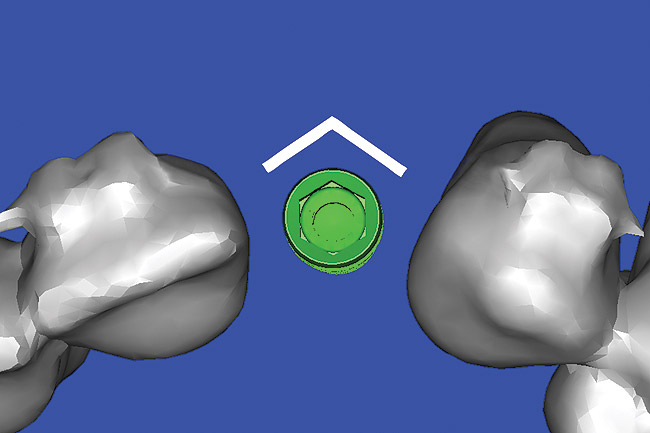

Using the interactive treatment-planning software application, the scan data was assimilated and both potential lateral incisor implant receptor sites were evaluated. It is a combination of the data and the methodology used to interpret the data that is the basis for defining a new paradigm in diagnosis and treatment planning. Proper evaluation of these images and correct use of the interactive treatment planning software tools is essential in creating a decision tree of treatment options. First, the data from the scan was reformatted into panoramic, axial, and cross-sectional images. The undistorted cross-sectional images revealed the residual alveolar bone in the area of the right lateral incisor. Then, a simulated schematic implant was placed within the bone with an abutment extension to help visualize the connection to the restorative position of the tooth (Figure 6). The Triangle of Bone® (TOB), a concept developed by the author to analyze bone quality, quantity, and disposition at prospective dental implant sites using CBCT scans, aided in determining available bone volume by defining a “zone” for proper implant placement18,19 (Figure 7).

After reviewing the CT data and the decision tree, the bone within the “zone” of the TOB was evaluated and found to be satisfactory for implant placement. Because the goal of implant dentistry is not the implant but the tooth that is placed, true restorative-driven implant dentistry must begin with the assumption that the implant position should remain consistent with the tooth it is replacing, and the final implant-supported restoration.12,22-26 The TOB aids the clinician in understanding the link between the implant position and the desired restorative goal. The base of the geometric shaped “zone” is visualized by starting at the widest area of alveolar bone facially and superiorly. The apex of the triangle is positioned to bisect the alveolar crest (Figure 7). The TOB, the overlay in the cross-sectional image, reveals whether adequate bone is available for implant placement. It also helps to identify concave facial bone defects, and accurately determine the width of bone at the crest. The author recommends using an interactive software application that provides the necessary measurement tools to accurately assess the bone anatomy.

Figure 7  SOFTWARE IMAGING The determination of the "zone" for proper placement.

Figure 7